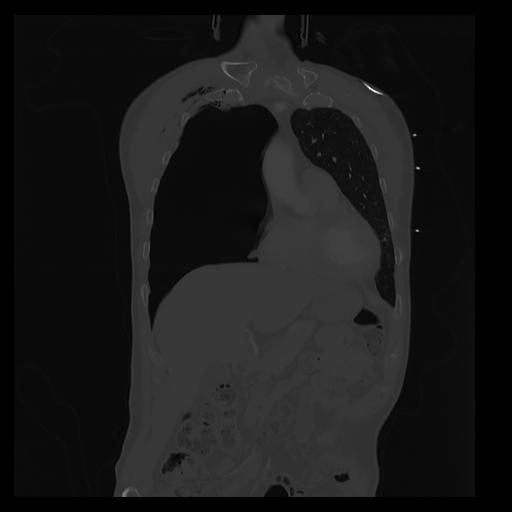

32 PULMON,CE,Coronal,3.000,PULMON,Coronal,